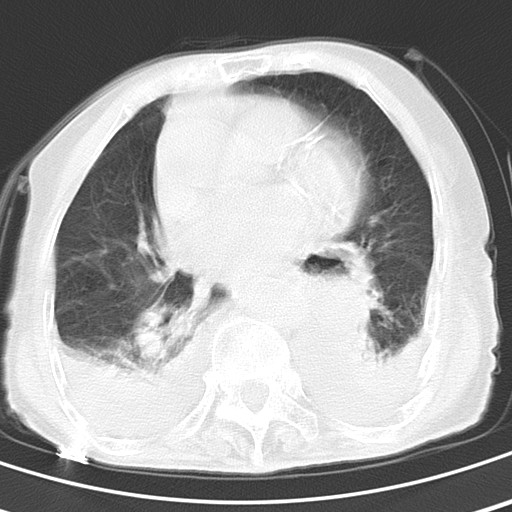

标题: CT21467:女,93岁,摔伤后检查。

女,93岁,摔伤后检查。

右肺炎症,心功能不全伴双侧胸腔积液,右下肺膨胀不全,食管裂孔疝,冠脉钙化,心包少量积液,左侧肋骨骨折,请上传骨窗.

右肺炎症,心功能不全伴双侧胸腔积液,右下肺膨胀不全,食管裂孔疝,冠脉钙化,心包少量积液,左侧肋骨骨折,右肩甲骨粉碎性骨折。93岁,高寿哇!

右肺炎症,心功能不全伴双侧胸腔积液,右下肺膨胀不全,食管裂孔疝,冠脉钙化,心包少量积液,左侧肋骨骨折,右肩甲骨粉碎性骨折。